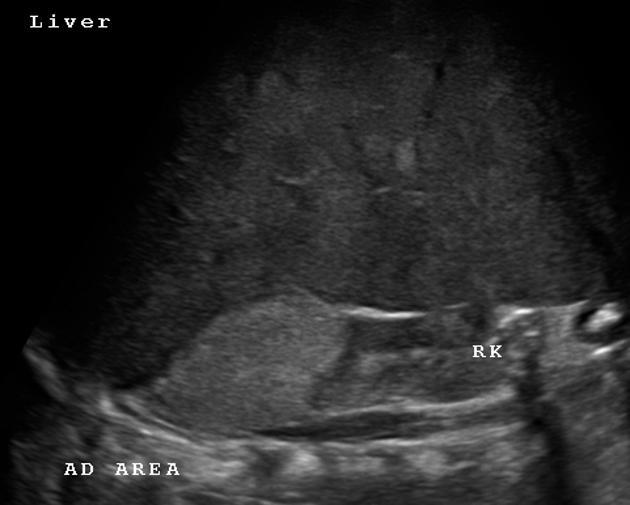

Mets to bones and renal/adrenal mass

Most likely neuroblastoma, Wilms usually does not go to bones (Except clear cell subtype).